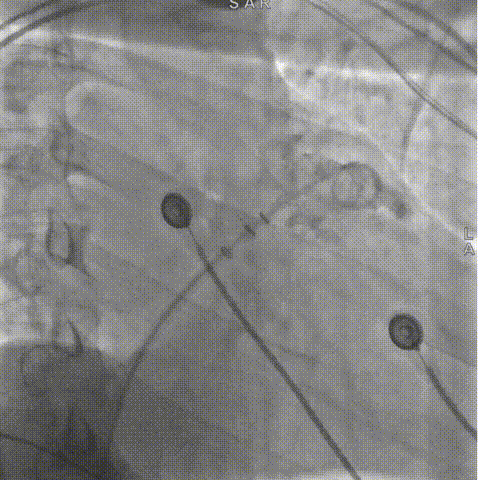

打开封堵伞后造影评估,锚定伞锚定在主干区域,再将封堵盘打开时脱落,遂选择更换为更换为更大号的LAMax LAAC® 2436封堵器。

封堵伞打开后造影

2133封堵器封堵盘放出时脱落

2133封堵器封堵伞打开后造影

LAAC® 2436封堵器锚定伞锚定在主干区域,再将封堵盘逐渐打开,保证封堵效果,封堵盘完全打开后造影,外盘覆盖外口,封堵完全,无残余分流。

更换2436封堵器后半打开封堵伞造影